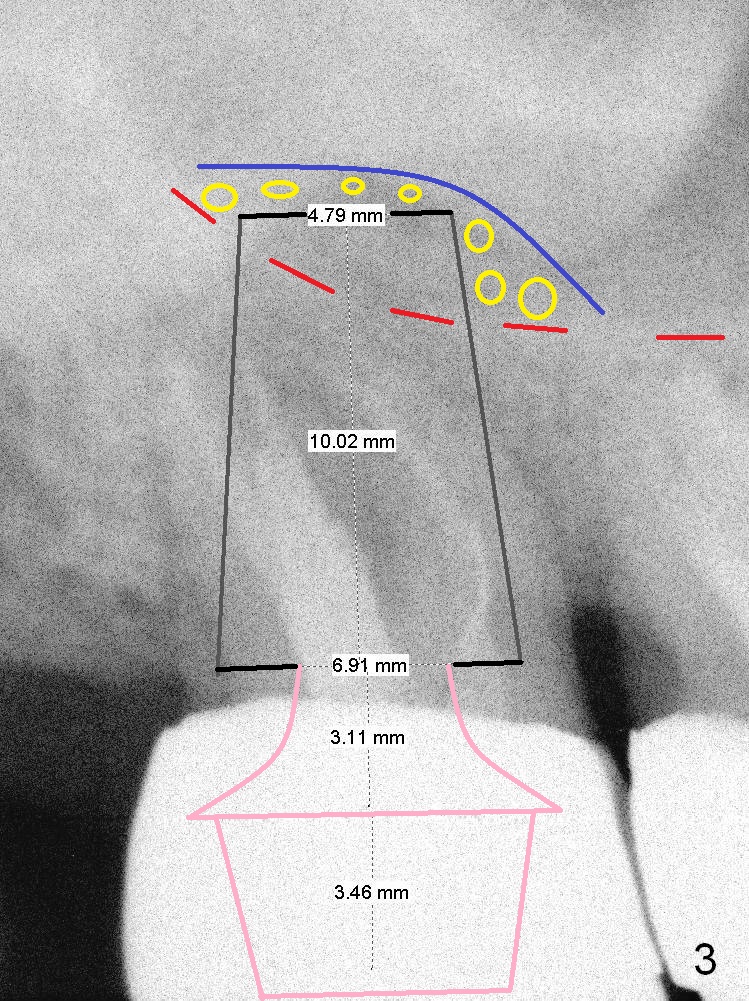

A 59-year-old man is a bruxer, fracturing the teeth #8 and 9.  Now the tooth #2 seems to have fractured (Fig.1).  Since the apices appear to protrude into the sinus, either 7x14 mm tissue-level (Fig.2) or 6.9x10 mm bone-level (Fig.3) implant will most likely penetrate the sinus floor (red dashed line).  To protect the sinus membrane, PRF membrane or plug (blue curved line) is to be placed prior to bone graft (yellow circles) and implant placement.  Prepare Magic Expanders and Magic Sinus Lifter.  Clindamycin will be used after extraction.  Since the roots of the upper 2nd molar usually fuse, prepare large gauzes for hemostasis.  Check the buccal and palatal walls for any defect.  Start osteotomy away from the defective wall.  Place the remaining PRF membrane for wall repair before bone graft.  Set stopper 2 mm short of the intended bone-level implant length.